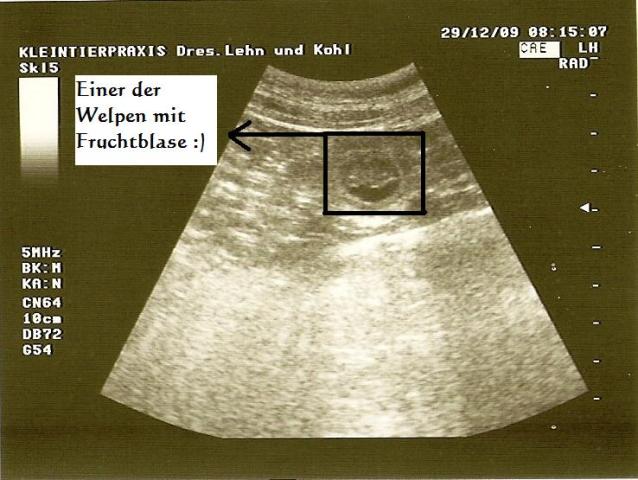

29.12.2009 (27. Tag)

Wir kommen gerade vom Ultraschall:

Lilli ist trächtig :):):):)

Ich kann Euch nicht sagen, wie ich mich FREUE!!!!

Die Welpchen sind noch ziemlich klein, wir denken es ist dann jetzt erst der ca.

25/26 Tag. Dann passt es auch mit Lillis Nahrungsverweigerung viel eher in den

normalen Ablauf der Trächtigkeit.

Wir haben 4-5 gesehen und die lagen eng, was bedeutet, es können noch

mehr sein. Wir gehen nächsten Dienstag nochmal zum Ultraschall.

JIPPI!!! :)